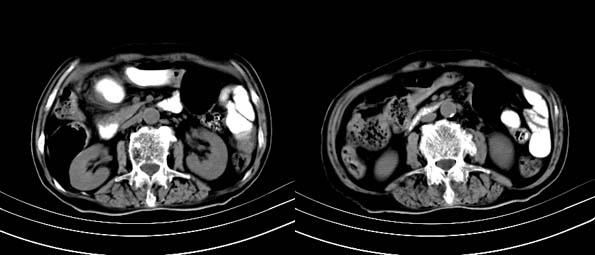

以下是引用bailaode在2008-6-12 22:10:00的发言:[br]资料中未提及患者有无急腹症体征,这个很重要。[br] ct表现:肝内境界模糊之低密度灶,内有含对比剂之液气平面.(提示肝内病灶与胃肠道沟通) [br] 1、根据“长城干红 ”所提供的资料“患者,女,74岁,黑便月余,消瘦,一般状况差,白细胞1万四千”,是否可认为是个慢性病程?那么我首先考虑:十二指肠结核,十二指肠--胆管瘘,继发胆道逆行感染肝脓肿形成。[br] 2、如有急腹症体征则考虑:十二指肠溃疡穿孔?十二指肠占位伴穿孔?

以下是引用拾荒者在2008-6-13 22:13:00的发言:[br]病灶与升结肠、肝脏及十二指肠关系密切,且结肠降段见造影剂影,支持结肠与十二指肠瘘形成,原因及原发病在哪不好定,不过,虽说有风险,但还是应该手术治疗,单纯抗感染估计不行。